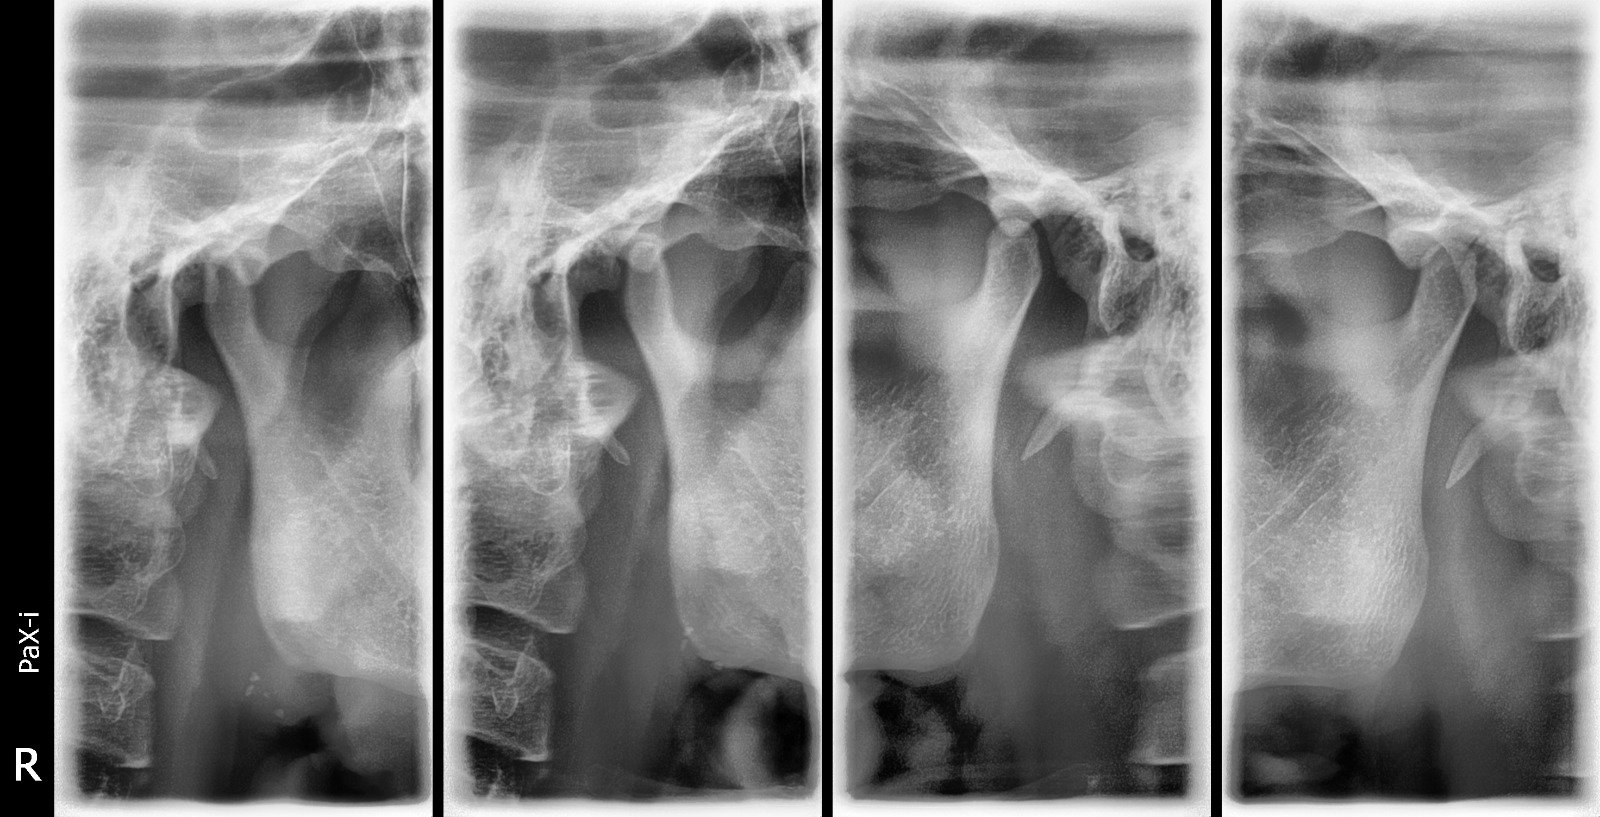

Imagen de Rx ATM Articulación Temporomandibular

Rx ATM Articulación Temporomandibular

Se utiliza para evaluar problemas de la articulación Temporomandibular , como chasquidos, dolor, limitación de apertura o desgaste articular

Costo: Consultar precio Duración: 10 min